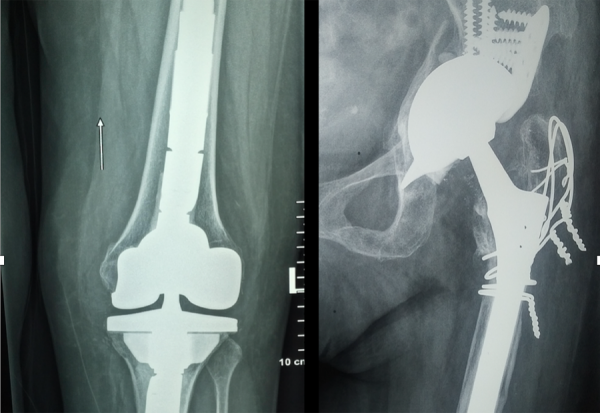

Οι αρθροπλαστικές ισχίου και γόνατος είναι από τις πιο επιτυχημένες επεμβάσεις στην ορθοπεδική, προσφέροντας ανακούφιση από τον πόνο και βελτίωση της κινητικότητας. Ωστόσο, υπάρχουν περιπτώσεις..κά

Η χειρουργική τραύματος αποτελεί έναν εξειδικευμένο τομέα της ορθοπεδικής που ασχολείται με την αποκατάσταση των οστικών και μαλακών ιστικών τραυματισμών που προκαλούνται από ατυχήματα, πτώσεις ή άλλες κακώσεις. Στόχος της είναι η άμεση...